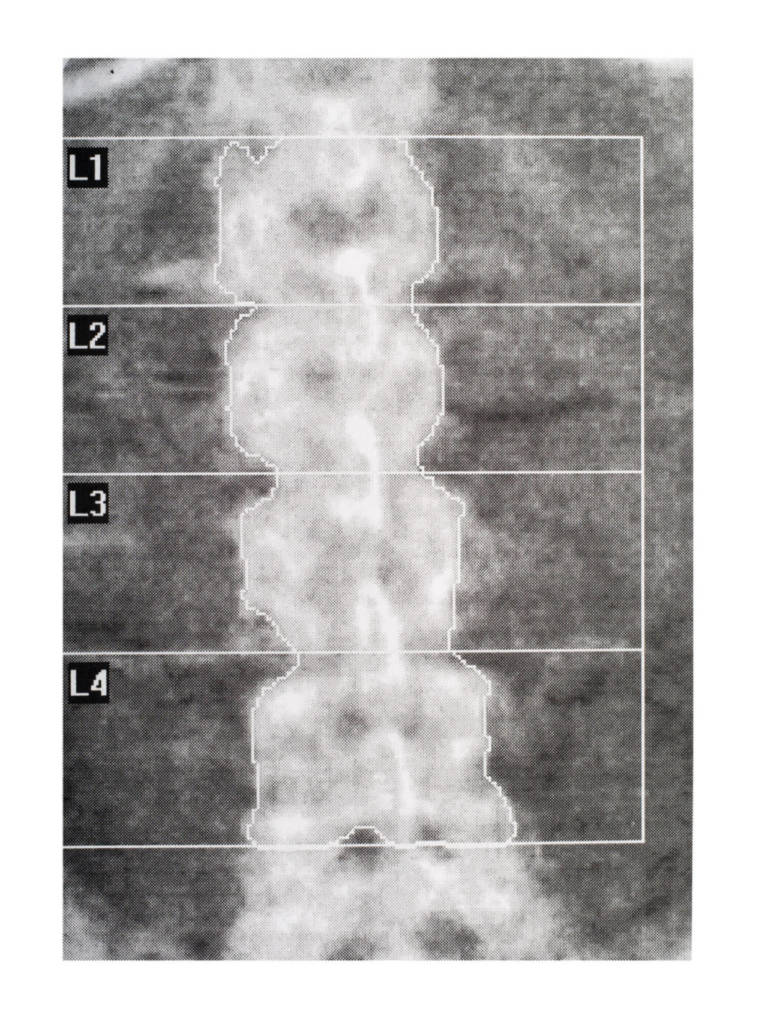

Per scoprire se si è a rischio di questo problema occorre quindi misurare la propria densità ossea stabilendo così se il livello è normale oppure no. E l’unico esame in grado di misurare con precisione la densità ossea e di effettuare la diagnosi precoce dell’osteoporosi, secondo l’Organizzazione Mondiale della Sanità, è proprio la Mineralometria Ossea Computerizzata, che da adesso abbrevieremo in MOC, considerata la metodica di riferimento.